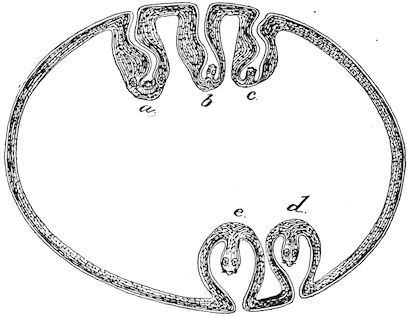

Fig. 1.—Rachitis in a young goat.